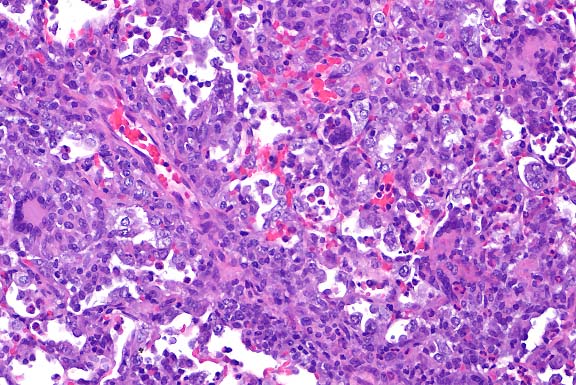

- Contributor's Diagnosis and Comments: Lung: Peribronchiolar

and interstitial pneumonia, granulomatous and eosinophilic, multifocal

(varied severity among sections).

Multifocally throughout the lung there are variably-sized, discrete,

noncaseating granulomas, mostly arranged around bronchioles,

but also present around or adjacent to vessels in the interstitium.

Granulomas are usually composed of tightly packed epithelioid

macrophages admixed with frequent multinucleated, Langhans-type

and foreign body-type giant cells and mild to moderate numbers

of eosinophils and neutrophils. Within granulomas, there are

occasional small central areas of necrosis characterized by accumulation

of cellular and nuclear debris, degenerate polymorphonuclear

leukocytes, and rarely, deposition of small amounts of brightly

eosinophilic, club-shaped, amorphous material (Splendore-Hoeppli

material; not present in all sections). In addition, throughout

the interstitium there are small to conspicuous perivascular

cuffs composed mostly of eosinophils and neutrophils, admixed

with occasional lymphocytes. In association with inflammatory

infiltrates, there is also mild to moderate alveolar histiocytosis,

mild to moderate interstitial edema, mild thickening of alveolar

walls with type II pneumocyte hyperplasia, and mild to moderate

hyperplasia of bronchiolar epithelia with mucous metaplasia.

- Case 19-1. Lung. Multifocally throughout the lung,

abundant macrophages, eosinophils, neutrophils and scattered

foreign body or Langhans giant cells expand or replace alveoli

and bronchioles.

- AFIP Diagnosis: Lung: Pneumonia, granulomatous and

eosinophilic, peribronchiolar and perivascular, multifocal, moderate,

with perivascular edema, Brown Norway rat, rodent.